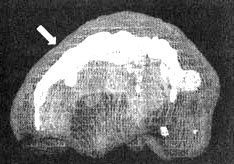

Трехмерное изображение — активный мозг, вид сверху

Иллюстрация к книге — Измените свой мозг - изменится и жизнь! [i_058.jpg]

Трехмерное изображение — активный мозг, вид спереди